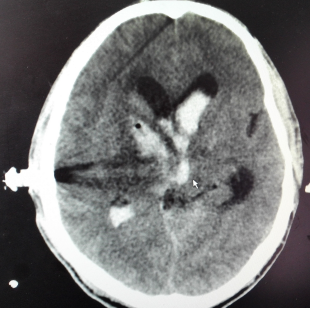

男性,50岁,右侧基底节区脑出血破入脑室、颅内高压,行颅内血肿微创清除术,有效清除了颅内积血,降低颅内压,患者恢复良好。

手术后